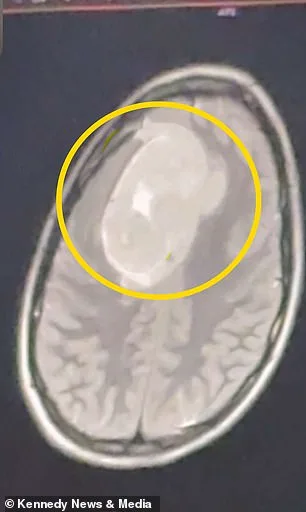

Her concerns grew when migraines returned during Christmas break. These episodes were debilitating, forcing her to lie in darkness, unable to move or breathe. "My head was shaking," she said. Frustrated by the lack of answers, she sought a second opinion. That decision proved pivotal. An MRI ordered in January 2026 revealed a tumor the size of a tennis ball, located in her left frontal cortex. The discovery was both shocking and urgent.

Medical professionals identified the growth as benign but emphasized its critical location. The tumor was pressing on the frontal cortex, an area vital for executive function, motor control, and language. "They told me to go to the emergency room immediately," Keating said. The situation was dire: prolonged pressure could lead to irreversible cognitive and motor impairments. A six-hour craniotomy followed, during which surgeons removed part of her skull to extract the tumor.